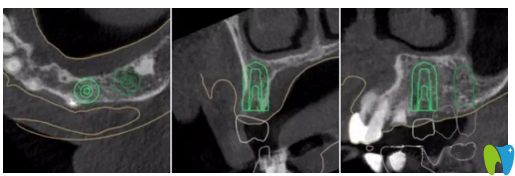

▲ 患者左上6牙位模擬種植圖

▲ 患者左上4牙位模擬種植圖

應(yīng)患者要求,并考慮到患者自身因素(高齡、高血糖及高血壓史),本著拜博口腔精 準(zhǔn)種牙的原則,擬定出數(shù)字化導(dǎo)板種植合并傳統(tǒng)修復(fù)的治療方案:

① 一期16,17,24,26數(shù)字化全程導(dǎo)板引導(dǎo)種植,二期16,17單冠修復(fù),24,25,26連橋修復(fù)。